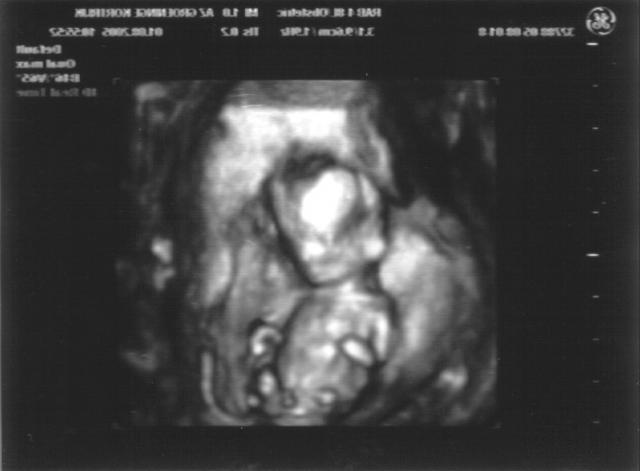

Nog een 33D echo - van de andere kant - als je de twee echo's samen bekijkt zie je dat de armpjes op en naar gaan

Echo_20050801c